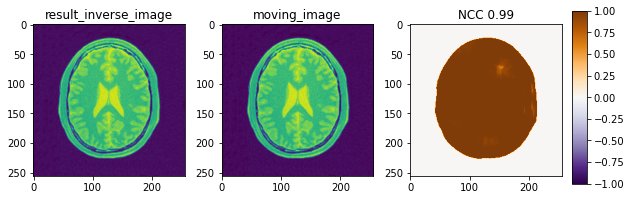

Inverse transform

変形のmetricをDisplacementMagnitudePenaltyに設定することで,逆変換が求められます.

変換$T_\mu$,座標$x$に対して,DisplacementMagnitudePenaltyとは,$T_\mu(x)-x$を表す変位に対するペナルティのことです.Registrationにおいては,入力画像と出力画像を同一に設定し,求めた順方向の変換を初期変換に与えます.

順方向変換が与えられた時,逆方向変換を手に入れられることを確認できました.